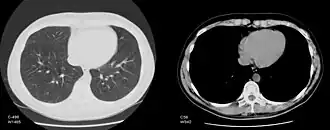

Изменение окна изображения

Обычный компьютерный монитор способен отображать до 256 оттенков серого цвета, некоторые специализированные медицинские аппараты способны показывать до 1024 оттенков. В связи со значительной шириной шкалы Хаунсфилда и неспособностью существующих мониторов отразить весь её диапазон в чёрно-белом спектре, используется программный перерасчёт серого градиента в зависимости от выбранного интервала шкалы. Чёрно-белый спектр изображения можно применять как в широком диапазоне («окне») денситометрических показателей (визуализируются структуры всех плотностей, однако невозможно различить структуры, близкие по плотности), так и в более-менее узком с заданным уровнем его центра и ширины («лёгочное окно», «мягкотканное окно» и т. д.; в этом случае теряется информация о структурах, плотность которых выходит за пределы диапазона, однако хорошо различимы структуры, близкие по плотности). Изменение центра окна и его ширины можно сравнить с изменением яркости и контрастности изображения соответственно.